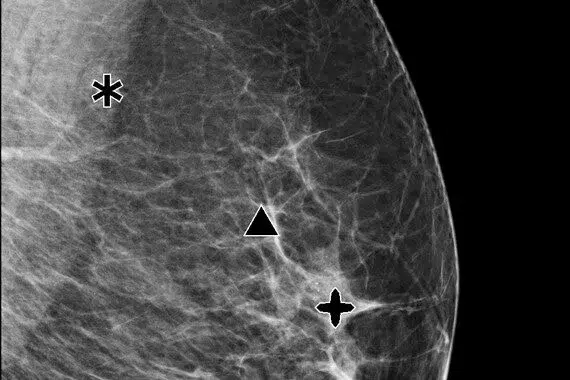

ImageChecker CAD software, which defines regions of interest in mammographic images to help radiologists minimize observational oversight, potentially reduces false negative readings.

• Identifies regions of interest in mammographic images to assist the radiologist.

• Analyzes and marks suspicious masses and clusters of calcifications.